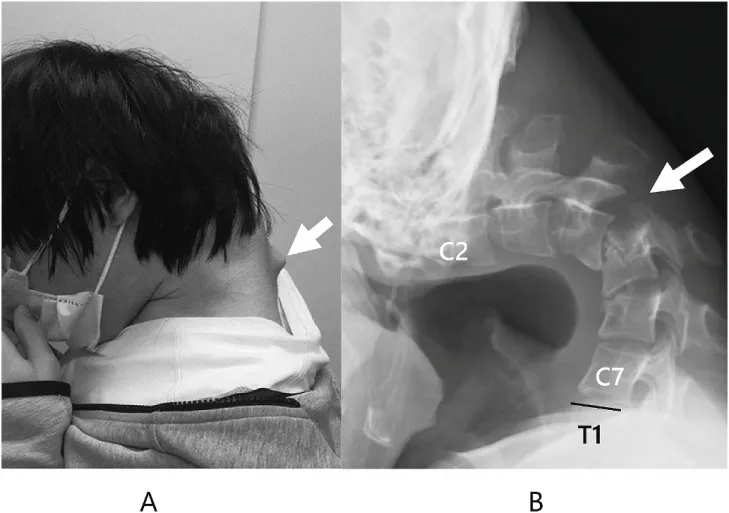

환자의 목에서 뿔처럼 솟아오르는 혹에 대해 의료진은 환자의 척추가 장기간의 부자연스러운 자세로 인해 ‘매우 확장’된 것으로 추정했다. 일본정형외과 학회지(JOS)의 사례 연구집 논문 캡처

거의 ‘ㄱ’자 형태로 심하게 꺾인 목, 뿔처럼 튀어나온 목뼈.

일본 규슈 오이타현의 오이타 정형외과를 찾은 남성 환자(당시 25세)는 한눈에 봐도 그 상태가 심각했다.

환자는 병원을 찾기 전 6개월 동안 심한 목 통증을 겪고 있었으며 고개를 들어 올릴 수 없다고 호소했다. 목이 너무 심하게 꺾여 그의 턱은 가슴에 거의 맞닿아 있었다.